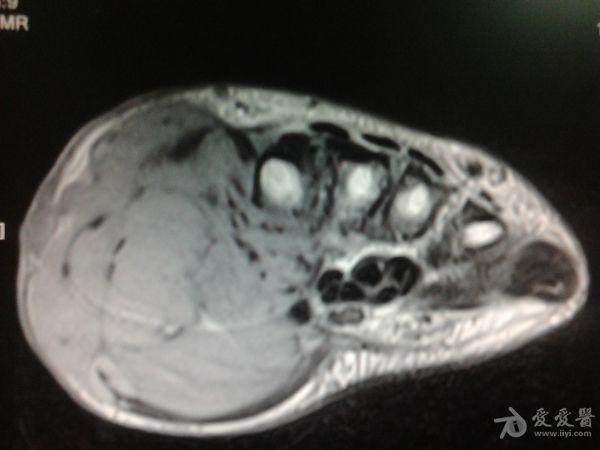

右第一掌骨、大多角骨肿瘤

男性患者,81岁,右手肿痛3个多月。无任何其它症状。体查:右手第一掌骨部肿胀明显,第一指活动受限,余四指活动可,腕关节活动小部分受限,活动时会痛。影像学检查如下。活检示:弥漫性大B细胞淋巴瘤。大家看看需不需要截肢?现在有人主张手术;有人主张不手术,直接化疗。大家有什么看法?